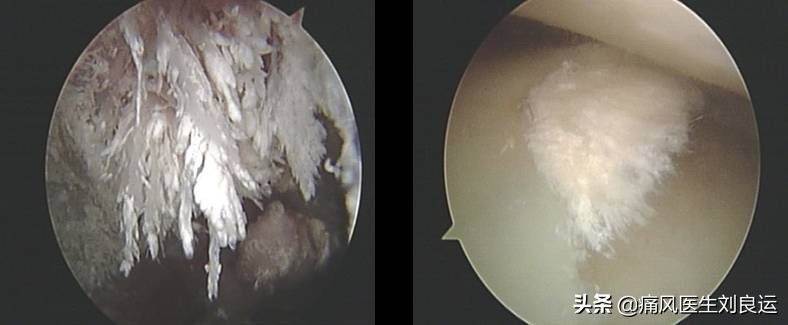

针刀镜下关节内散在尿酸盐结晶

针刀镜下痛风石沉积关节的尿酸盐结晶

针刀镜通过钝剥关节内滑膜、软骨表面及充分灌洗关节腔,清除关节滑液及滑膜、软骨表面的致炎因子和沉积物,减轻其引起的机体免疫应答反应,从而遏制疾病进展。同时,通过解除关节内外的组织黏连、剥削增生的滑膜和尿酸盐结晶,改善关节活动度,恢复关节功能。针刀镜能明显缓解难治性痛风石关节炎患者关节疼痛和改善关节功能,结合药物治疗,能减轻全身炎症程度和降低血尿酸水平。

在镜下对附着在软骨、滑膜及软组织中的痛风石进行剥离、刮除、清理